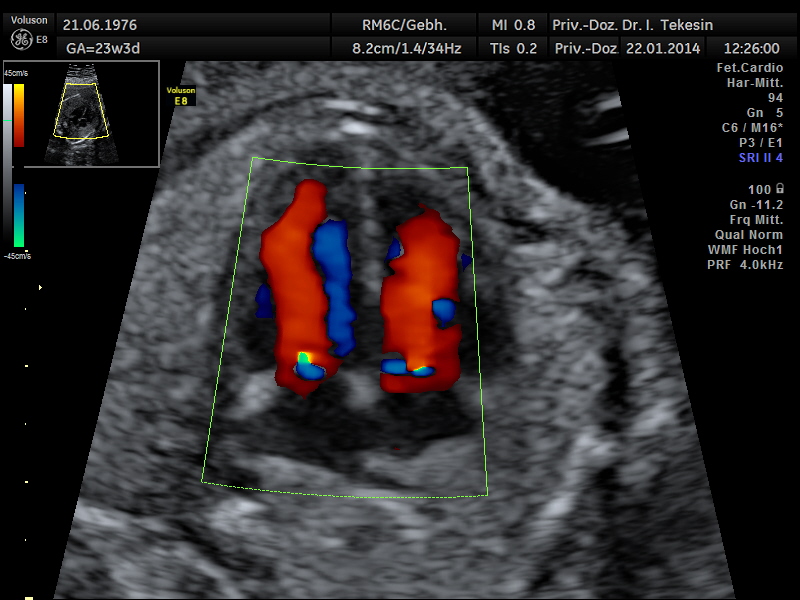

Ein weiterer Bestandteil der weiterführenden Ultraschall-Diagnostik ist die Beurteilung des kindlichen Herzens und der großen Blutgefäße, die fetale Echokardiographie. Dabei untersuchen wir die Lage, Größe und Symmetrie des Herzens, Anatomie der Herzstrukturen, Funktion der Herzklappen, Herzfrequenz und die Lage der großen Gefäße. Mit Hilfe der farbkodierten Doppler-Sonographie des Herzens werden weitere Details untersucht: die Funktion der Herzkammern, Herzscheidewände, Blutflüsse im Herzen und Blutflüsse in den großen Gefäßen.

Dopplersonographie

Auch das Durchblutungsverhalten in der Nabelschur und in den Gebärmuttergefäßen wird mit Hilfe des Doppler-Ultraschalls dargestellt. Diese Untersuchung ist eine ergänzende Untersuchung im Rahmen der US-Feindiagnostik und ermöglicht eine Beurteilung des Blutflusses in den kindlichen und mütterlichen Gefäßen mittels einer speziellen Technik. Bei dieser Untersuchung wird die Blutströmung farbig und akustisch dargestellt. Die Geräusche, die man während der Untersuchung hören kann, entstehen durch technische Effekte (Doppler-Effekt), welche der Untersucher und die werdende Eltern hören können, jedoch nicht das ungeborene Kind.

Durch Darstellung der Blutflussmuster in den mütterlichen Gefäßen (Arterie uterina rechts und links) zwischen der 20.-25. SSW können Feten mit dem Risiko einer späteren Mangelversorgung (Plazentainsuffizienz) entdeckt und somit im weiteren Schwangerschaftsverlauf optimal überwacht werden. Ein erhöhtes Risiko für die Entwicklung einer Präeklampsie (mütterlicher Bluthochdruck und Eiweißausscheidung im Urin) kann ebenso festgestellt werden.

Die Beurteilung des Blutflusses in den kindlichen Gefäßen (Nabelschnurarterie [A. umbilicalis], A. cerebri media und Ductus venosus) ermöglicht eine Aussage zur Versorgung des ungeborenen Kindes. Die Doppleruntersuchung kann in unterschiedlichen Zeitpunkten der Schwangerschaft durchgeführt werden.

Normaler Vierkammer–Blick mit Farbe

Normaler Vierkammer-Blick mit Farbe